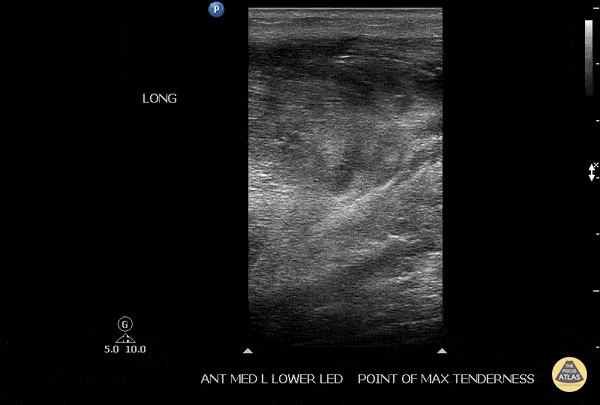

Musculoskeletal - Soleus Hematoma

This is a patient who presented to the emergency department with left calf pain, swelling, previous history of DVT and currently on Xarelto. A patient with such a presentation would cause concern for ruling out a new DVT however a subsequent DVT scan proved to be negative. The key approach for this patient was to evaluated the area of maximal tenderness with ultrasound, which in this case, revealed a hematoma within their soleus muscle! Image courtesy of Robert Jones DO, FACEP @RJonesSonoEM Director, Emergency Ultrasound; MetroHealth Medical Center; Professor, Case Western Reserve Medical School, Cleveland, OH View his original post here